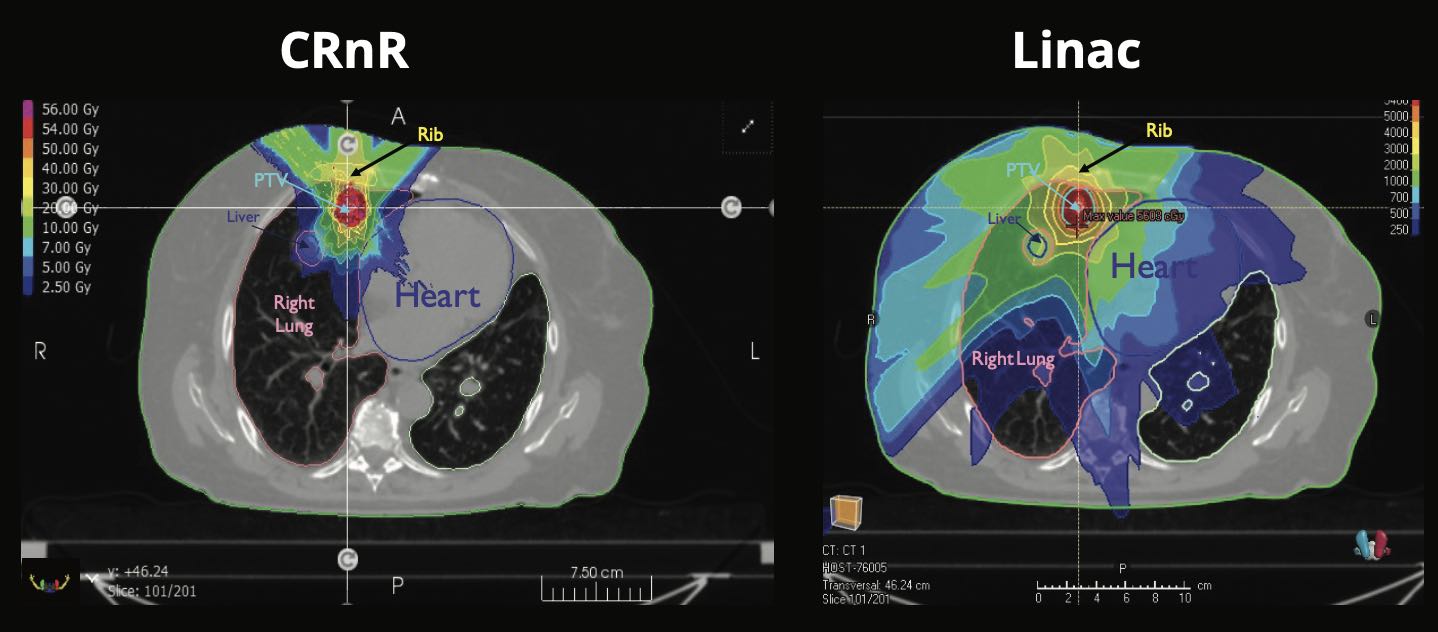

CRnR’s unique beam structure produces a Photon Spread Out Peak (PSOP) effect which closely replicates the effects of the Proton SOBP with a region of maximum dose at the target and a reduced dose before and after the target.

Safer treatment: Superior (reduced) dose to neighbouring tissue thanks to the Bragg Peak Like profile of the focused x-ray photon beam. See Isodose comparison in sample lung case below, showing reduced radiation to the heart, lung and liver vs Linac.